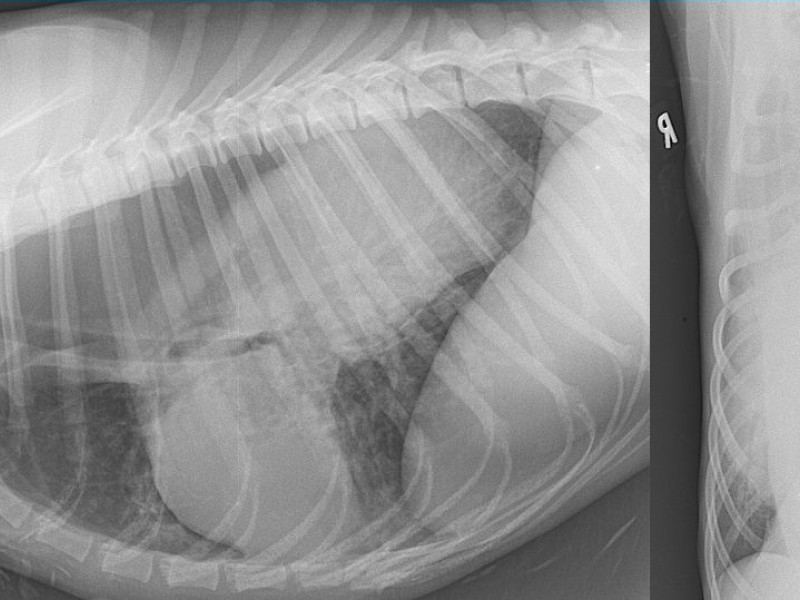

Chest radiographs: left lateral and ventrodorsal.

Presence of a very large ovoid mass within the dorsal part of the caudal mediastinum and of general gas dilation of the esophagus (tracheal stripe sign).

Moreover the gastric bulla is not recognized in the cranial abdomen.